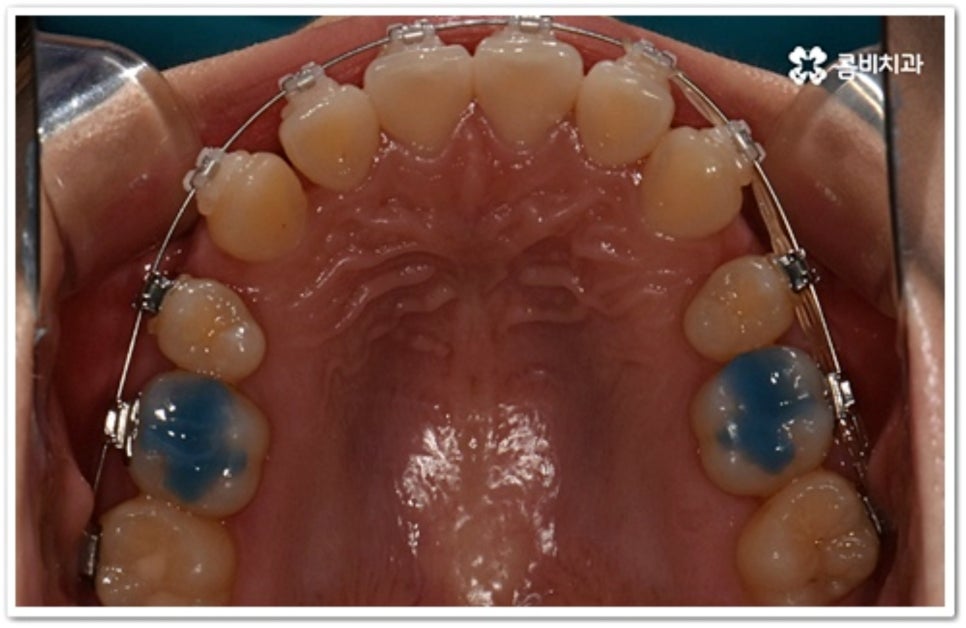

그러나 만약 덧니가 많고 부정 교합 정도가 심하거나 치아가 고르게 배열될 공간이 크게 부족하다면 덧니 발치 교정 치료를 진행하게 되는데, 이때 보통 치아 중에 기능이 가장 적은 소구치를 우선적으로 발치하게 되지만 (사진에서 확인할 수 있는 케이스) 환자분들의 상황에 따라 필요 없는 사랑니를 발치하고 어금니부터 뒤로 밀어 자리를 잡아주거나 충치 또는 짧아진 치근 등으로 심하게 손상된 치아가 있는 소구치를 우선적으로 발치하여 교정 치료를 진행하기도 하고, 필요시 임플란트와 병행하여 치료를 진행하는 경우도 있습니다. 따라서 먼저 자신의 상황에 대해서 면밀하게 검진을 받아보고 자세한 치료 계획에 대해서 의료진과 충분하게 상담해 보시는 게 좋을 거예요.

치아는 제자리로 돌아가려는 성질을 가지고 있어서 덧니 발치 교정이 끝난 후 일정 기간 동안은 유지 장치를 착용하여 이를 예방하고 정기 검진을 꼬박꼬박 받으면서 사후 관리를 철저하게 해 주는 게 좋을 거예요. 유지장치에는 고정식과 가철식이 있는데 치아 안쪽에 얇은 철사를 붙이는 고정식 (사진에서 볼 수 있는 사례) 은 앞니가 틀어지는 것을 방지해 주고, 뺐다 꼈다 하는 가철식은 교정 치료할 때 악궁 확장을 한 경우 전체 치열을 유지하기 위해 필요한 방식이라고 할 수 있어요. 환자분들 각각의 치료 과정이나 구강 상태에 따라 둘 중 하나를 선택하거나 두 가지 다 해야 하는 경우가 생길 수 있습니다.